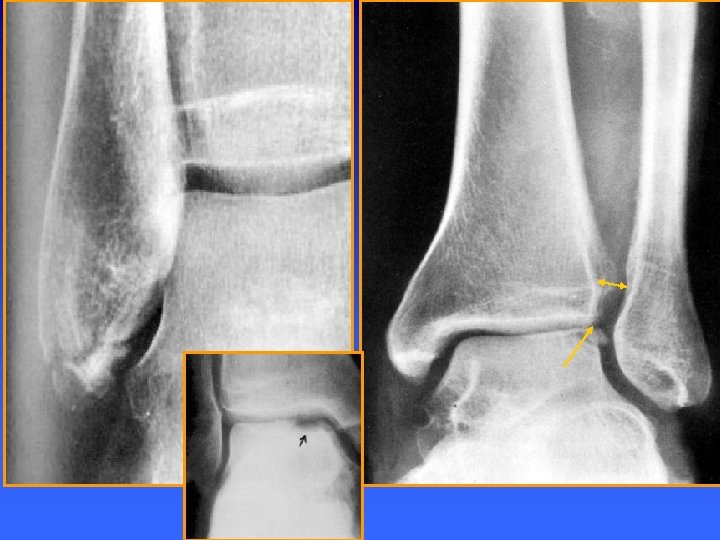

Entorse tibio-fibulaire inférieure n RX: n n n Diastasis tibio-fibulaire (il peut ne pas se voir !) Fractures Echographie: n Epaississement du tibio-fibulaire antérieur

RX ET ARTHRO-SCANNER Clarté sous chondrale, ostéosclérose sous chondrale